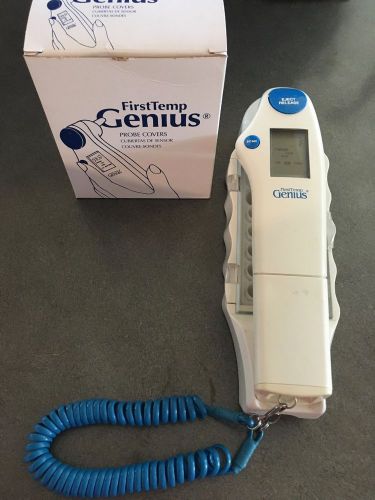

First Temp Genius Temperature Infrared Tympanic Thermometer Mod 3000A